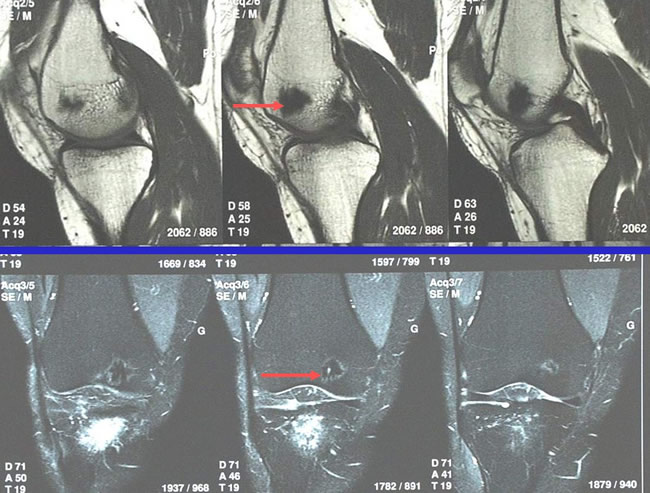

Navigation fluoroscopique : IRM

Aspect tumoral du condyle fémoral interne.

L'intérêt de la chirurgie assistée par ordinateur dans l'excision de l'Ostéome Ostéoïde. Navigation scannographique et fluoroscopique: 2 cas cliniques A.Eid MD; A.Badulescu MD; T.Martinez MD; P.Girard MD; P.Merloz MD - AOLF 2002